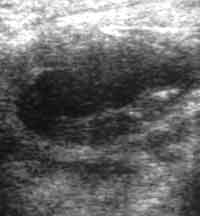

Абсцесс передней брюшной стенки.

Рис. 3. После дренирования полость абсцесса уменьшилась. Режим "увеличения".